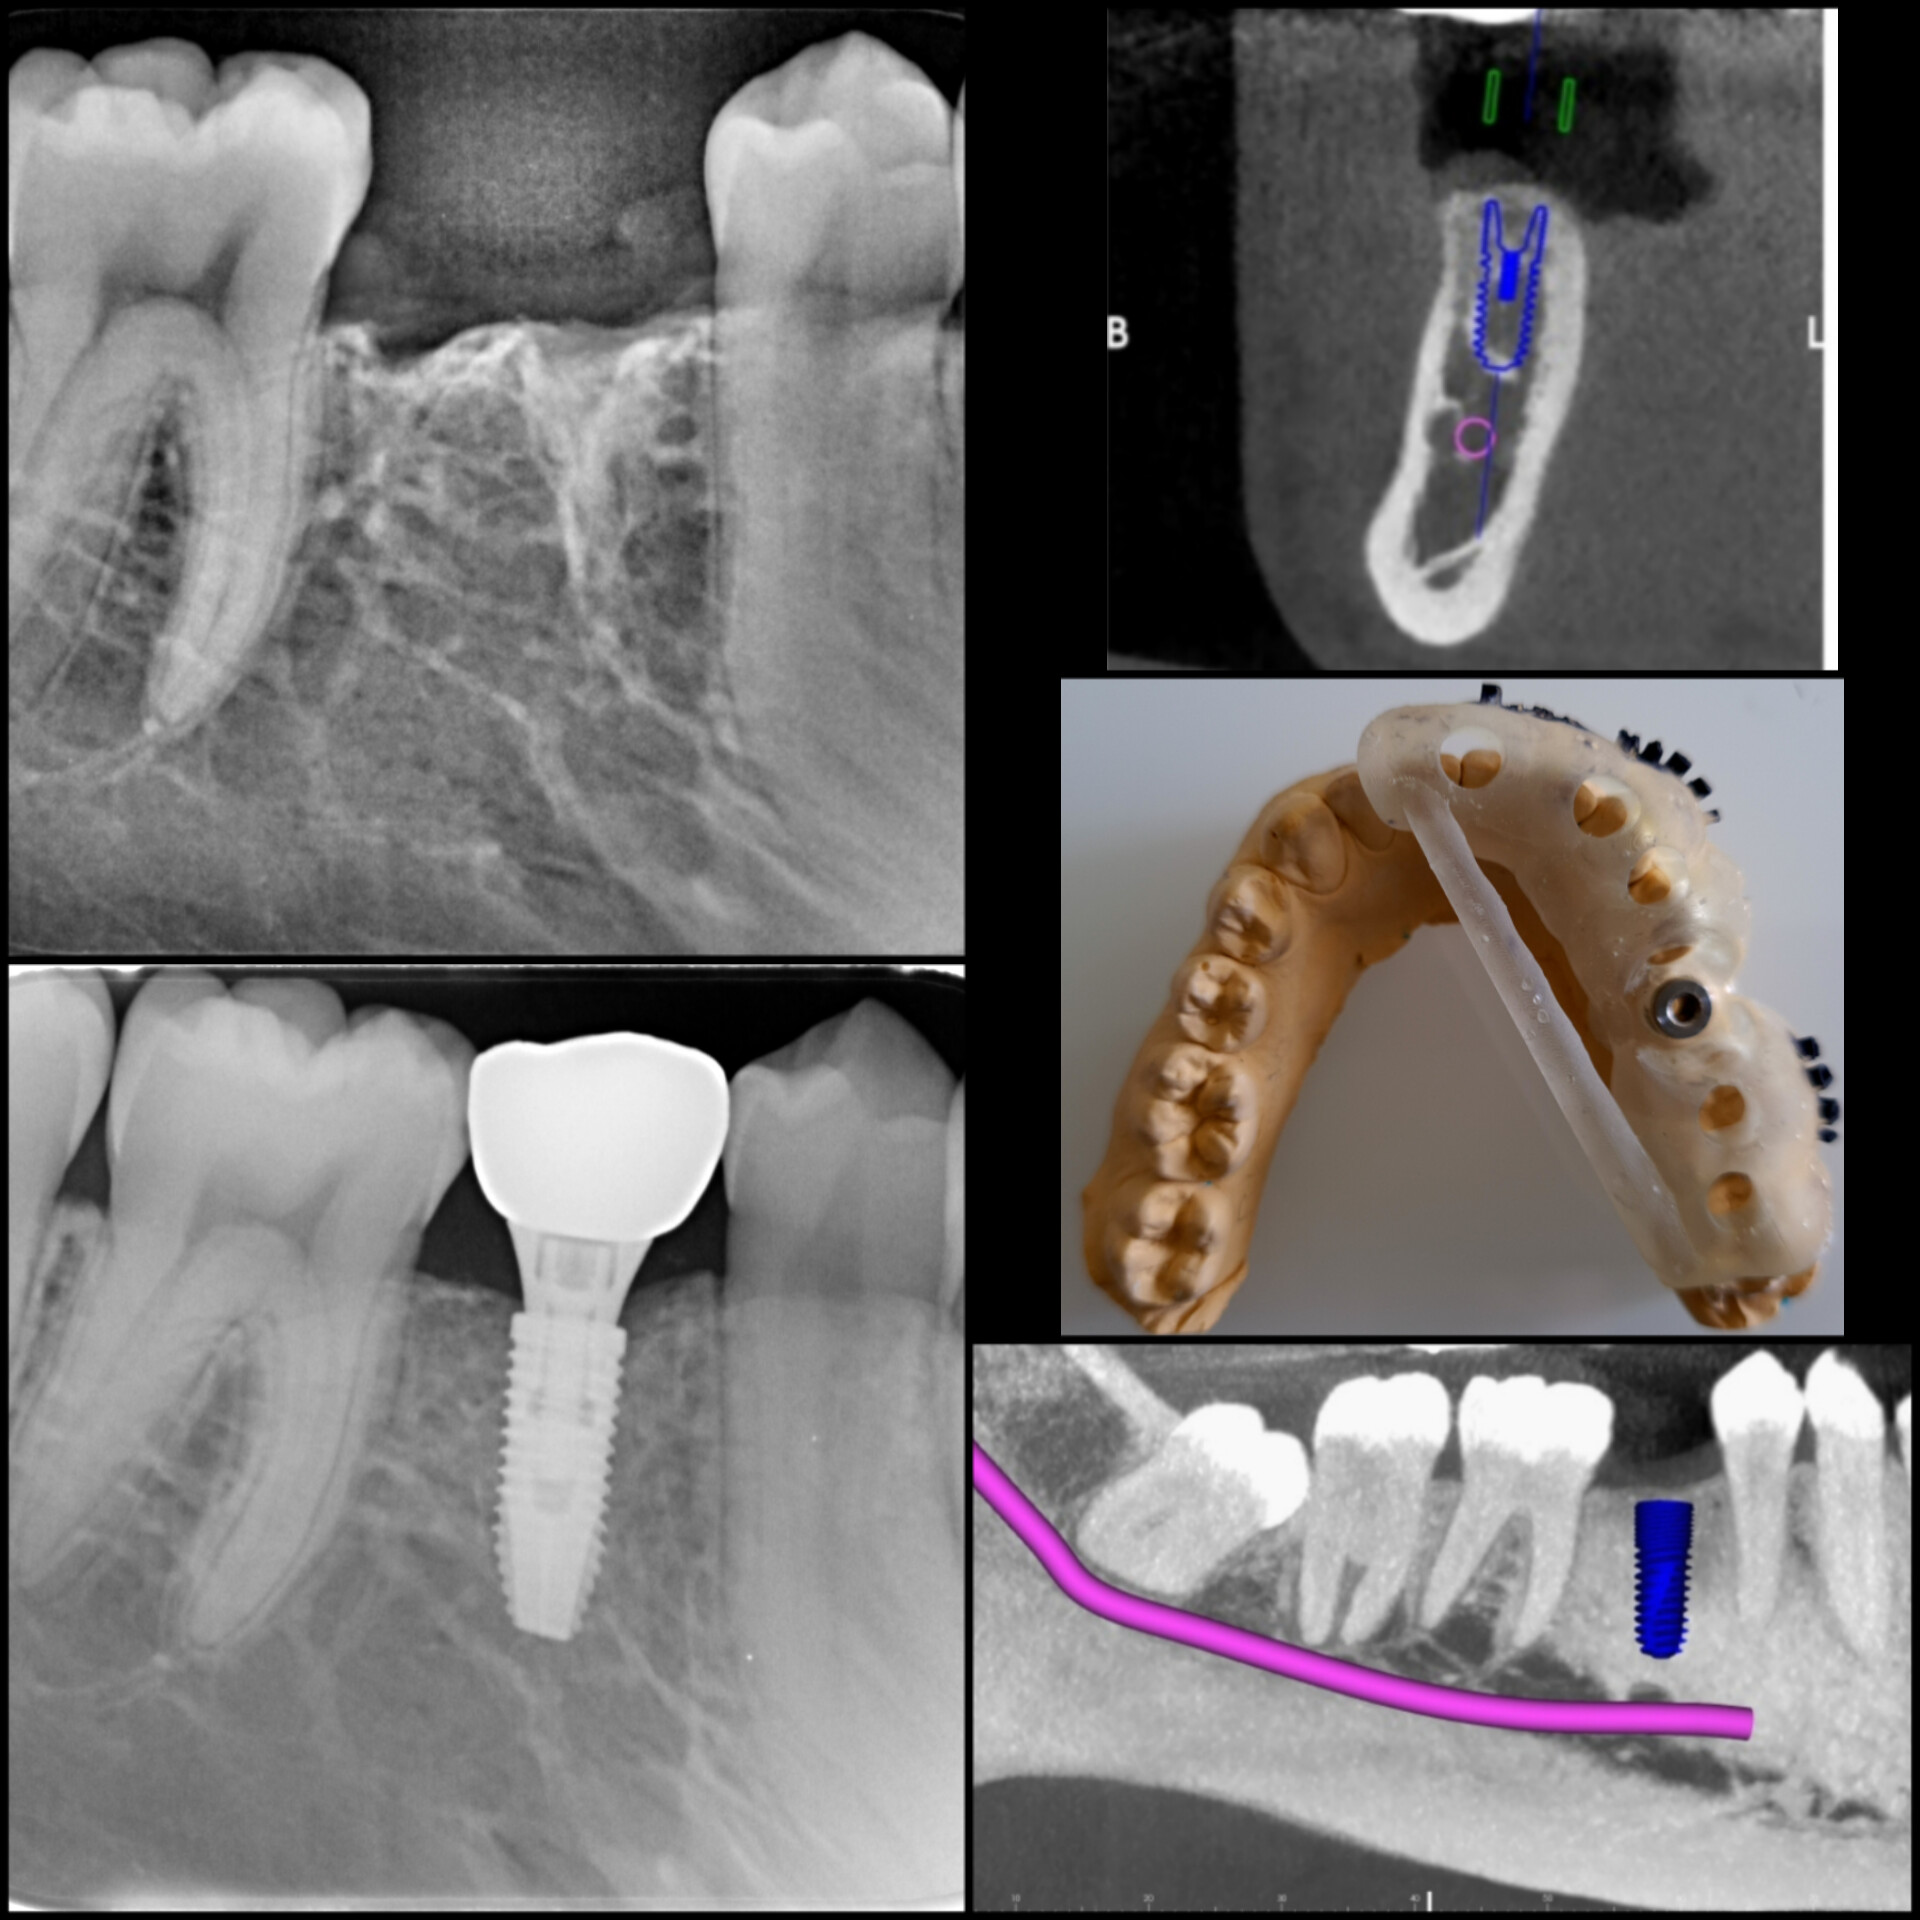

1. We do all implant placement by ‘Robotic Guided Surgery’ for precise, painless, bloodless, stitchless, and fast recovery.

We first create a virtual plan using the implant planning software (Nobel Guide) and also give options of Computer Guided Surgery.

1. No stitches and no gum opening surgery is required.

2. Very fast surgery through the small hole.

3. Less Painful surgery.

4. Very Less post-op discomfort.

5. Flapless procedure – Fast healing.

6. Precise implant placement.

7. No chances of trauma to surrounding vital tissues.